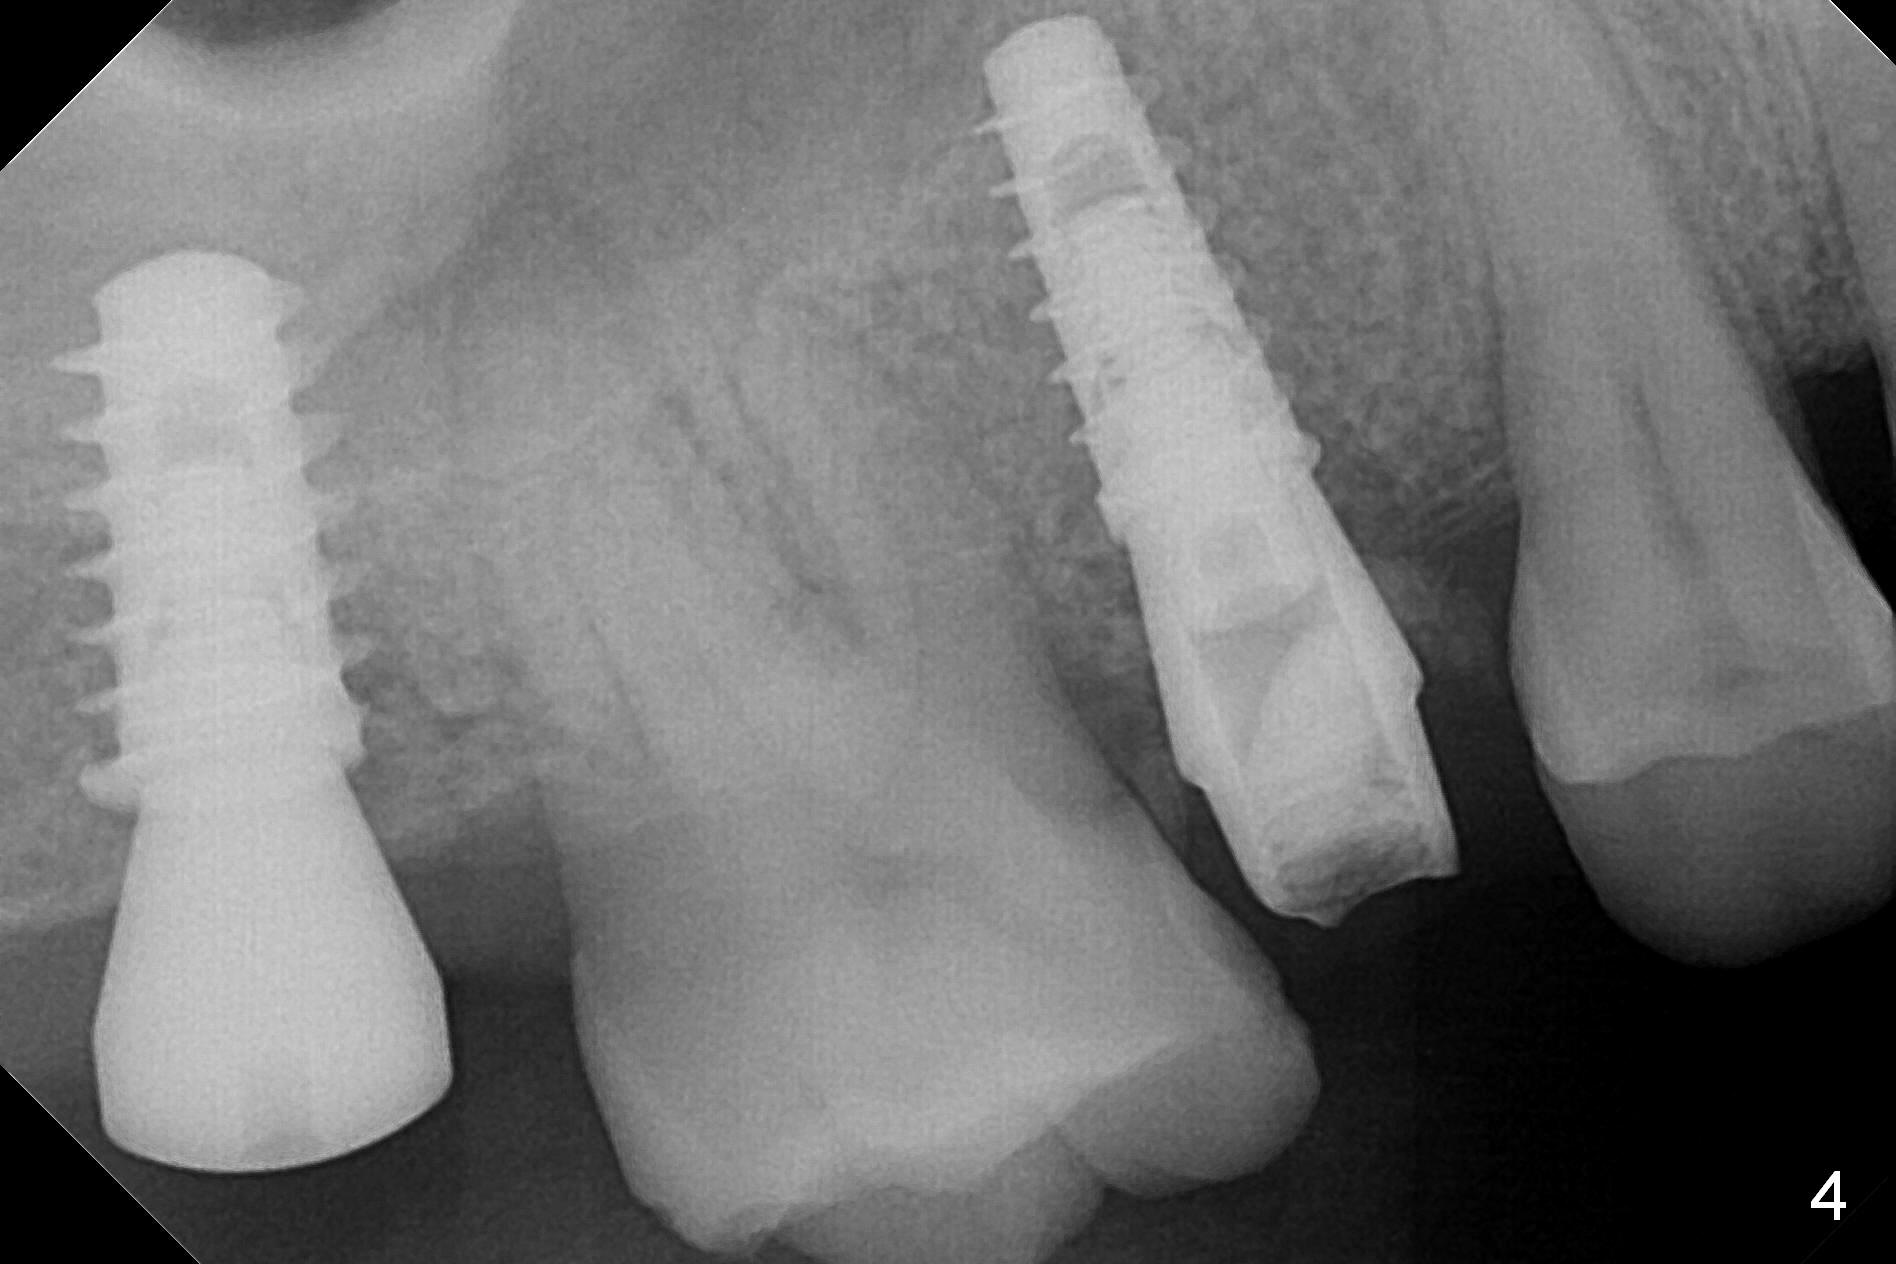

Since the ridge at the site of #2 is wide (Fig.1), Magic Split is used for access and bone density determination. In fact it enters for 9 mm (gingival level), followed by Magic Expander (ME) 3 mm (Fig.2 *). The center of the latter is 3.9 mm from the distal surface of the tooth #3. Lindamann bur is used to move the osteotomy distal, followed by sequential use of MEs until 4.3 mm one. When a 5x9 mm dummy implant is placed, its center is somewhat mesial (Fig.3 brown line). What needs to be done is change the trajectory to the red line so that the coronal end of the definitive implant (5.5x9 mm) will be placed evenly subcrestal (Fig.4,5). It is what happens, although slightly too subcrestal. Insertion torque is <35 Ncm; a 6x4 mm healing abutment is placed. ME 4.8 mm has to be tapped for 13 mm from gingival margin in order to let the implant penetrate the sinus floor. IBS implants seem to lack self tapping ability. Its tap drills should possess this capacity. Allograft/autogenous bone (harvested from dummy implant) is placed prior to implantation. The patient returns for impression 6 months postop (Fig.6,7; #4). A 5x4(3) mm abutment is placed; its height is reduced as well as the opposing supraerupted tooth (Fig.5) prior to impression.